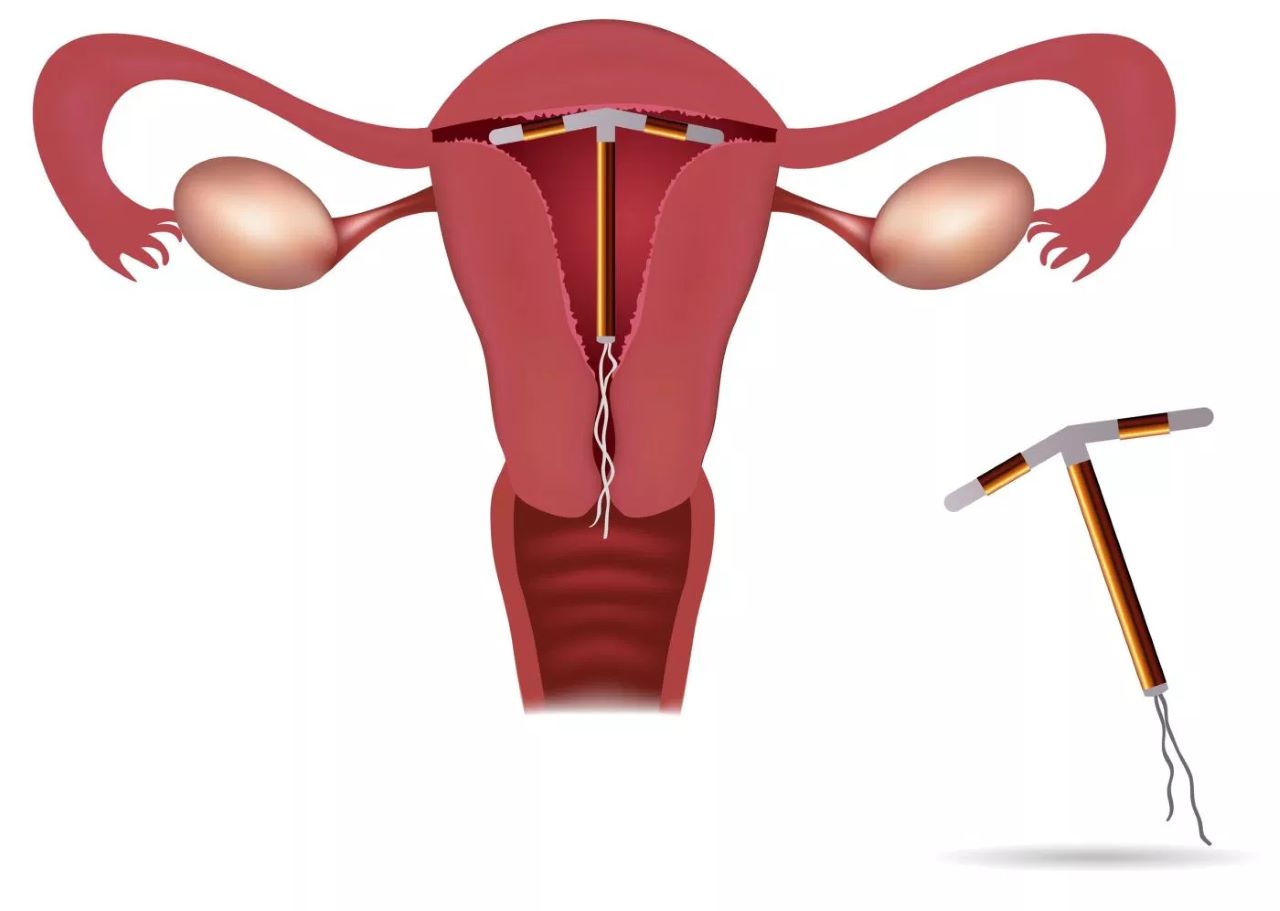

Đặt vòng tránh thai dạng (T) chứa đồng

Hiệu quả tránh thai cao lên tới 98%. Đây là một dụng cụ đặt trong tử cung, hoạt động dựa trên cơ chế ngăn cản quá trình thụ tinh và làm tổ của trứng Hạn sử dụng: Tối đa 10 năm